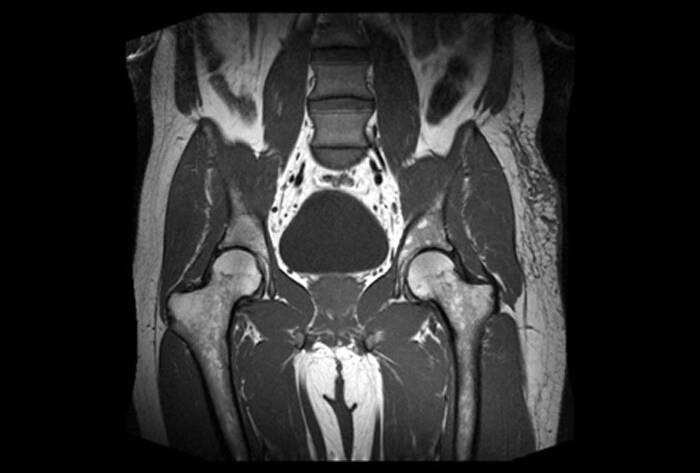

Kadın sağlığı denildiğinde akla gelen en önemli bölgelerden biri pelvik bölgedir. Rahim, yumurtalıklar, tüpler ve mesaneyi kapsayan bu bölgedeki sorunlar, bazen rutin bir muayene veya ultrasonla tam olarak anlaşılamayabilir. İşte bu noktada Pelvik MR (Manyetik Rezonans), sunduğu yüksek çözünürlüklü görüntülerle modern tıbbın en güçlü teşhis araçlarından biri olarak devreye girer.

Peki, Pelvik MR nedir ve kadın…